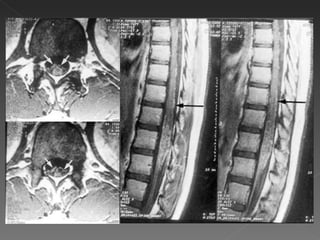

Tumefação variável da medula espinhal. Áreas difusas ou multifocais de sinal brilhante anormal em sequências pesadas em T2, podendo se estender por vários segmentos da medula espinhal. Nos casos agudos, pode se observar captação de contraste, indicativa  de ruptura da barreira hematencefálica associada a inflamação perivenosa. Também exclui compressão de medula.

Tumefação variável damedula espinhal. Áreas difusas ou multifocais de sinal brilhante anormal em sequências pesadas em T2, podendo se estender por vários segmentos da medula espinhal. Nos casos agudos, pode se observar captação de contraste, indicativa de ruptura da barreira hematencefálica associada a inflamação perivenosa. Também exclui compressão de medula.